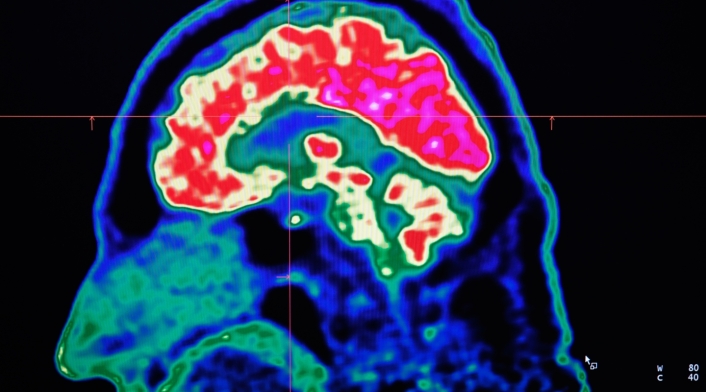

Tras ser llevado al hospital, los médicos le explicaron que había disecado su arteria, lo que había provocado tres accidentes cerebrovasculares en la parte inferior del cerebelo, la parte del cerebro responsable de la coordinación y el movimiento.